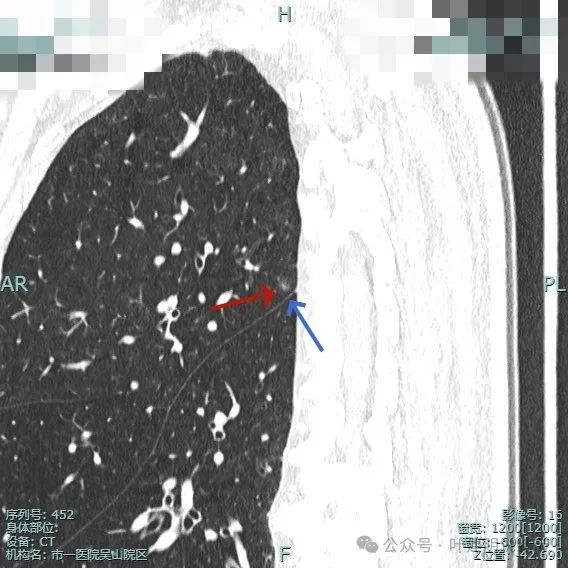

右上结节虽小,但轮廓较清,邻近有小血管走行,两者之间有缝隙,说明不太像肺内淋巴结或普通急性炎症。

其实密度不太纯,边缘显毛糙,离叶间裂近,但叶间裂无明显牵拉。

中间似有血管穿行,离胸膜也近的,整体轮廓较清。

此灶考虑肿瘤范畴的可能性大,微浸润性腺癌或不典型增生可能性大,有时细支气管腺瘤也会类似表现。总体可先随访,反正它也不是主病灶。